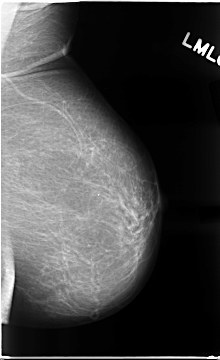

C_0073_1.LEFT_MLO

LEFT_MLO LINES 4672 PIXELS_PER_LINE 2848 BITS_PER_PIXEL 12 RESOLUTION 50 NON_OVERLAY